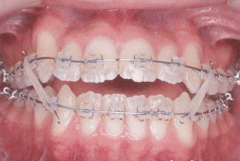

前牙开颌矫正会痛吗?

前牙开颌在临床上并不常见,但是它不但影响外貌美观,还会影响口腔咀嚼功能...【详细】